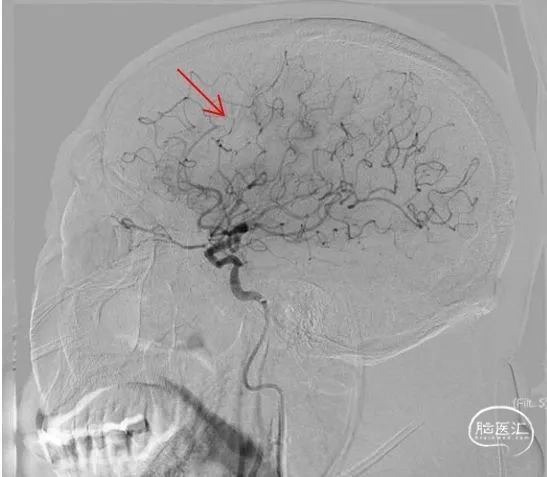

释放6*30mm心玮捕星颅内取栓支架,采用SWIM技术进行取栓,大脑中动脉再通良好,大脑前动脉A3段存在血栓逃逸(红色箭头),动脉团注替罗非班注射液10ml。

释放心玮灵笼栓塞保护器,采用5*30mm心玮披荆颈动脉球囊扩张导管再次进行扩张,随后释放6-8*40mm颈动脉支架,再次通过导引导管造影,血管再通良好。